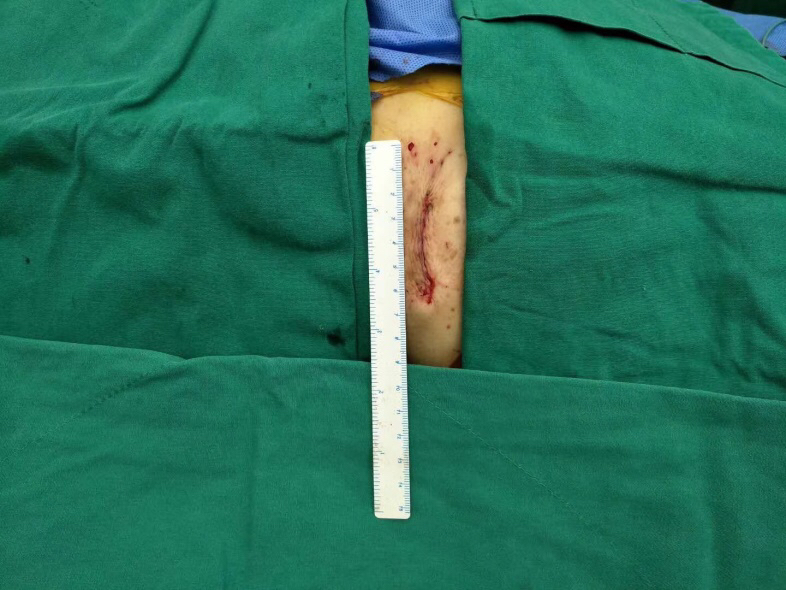

整个手术过程非常顺利,仅耗1个半小时,胸骨肋骨无任何破坏,也无需体外循环,出血量未超过100ml。术后2小时老太太完全清醒过来并拔除气管插管,还能与医务人员轻松交谈。

图片说明:胸前4厘米的手术切口。